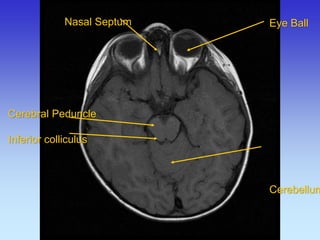

Eye Ball

Cerebral Peduncle

Temporal Horn Lateral Ventricle

Occipital Lobe

Lateral Sulcus (Sylvian)

Inferior Colliculus